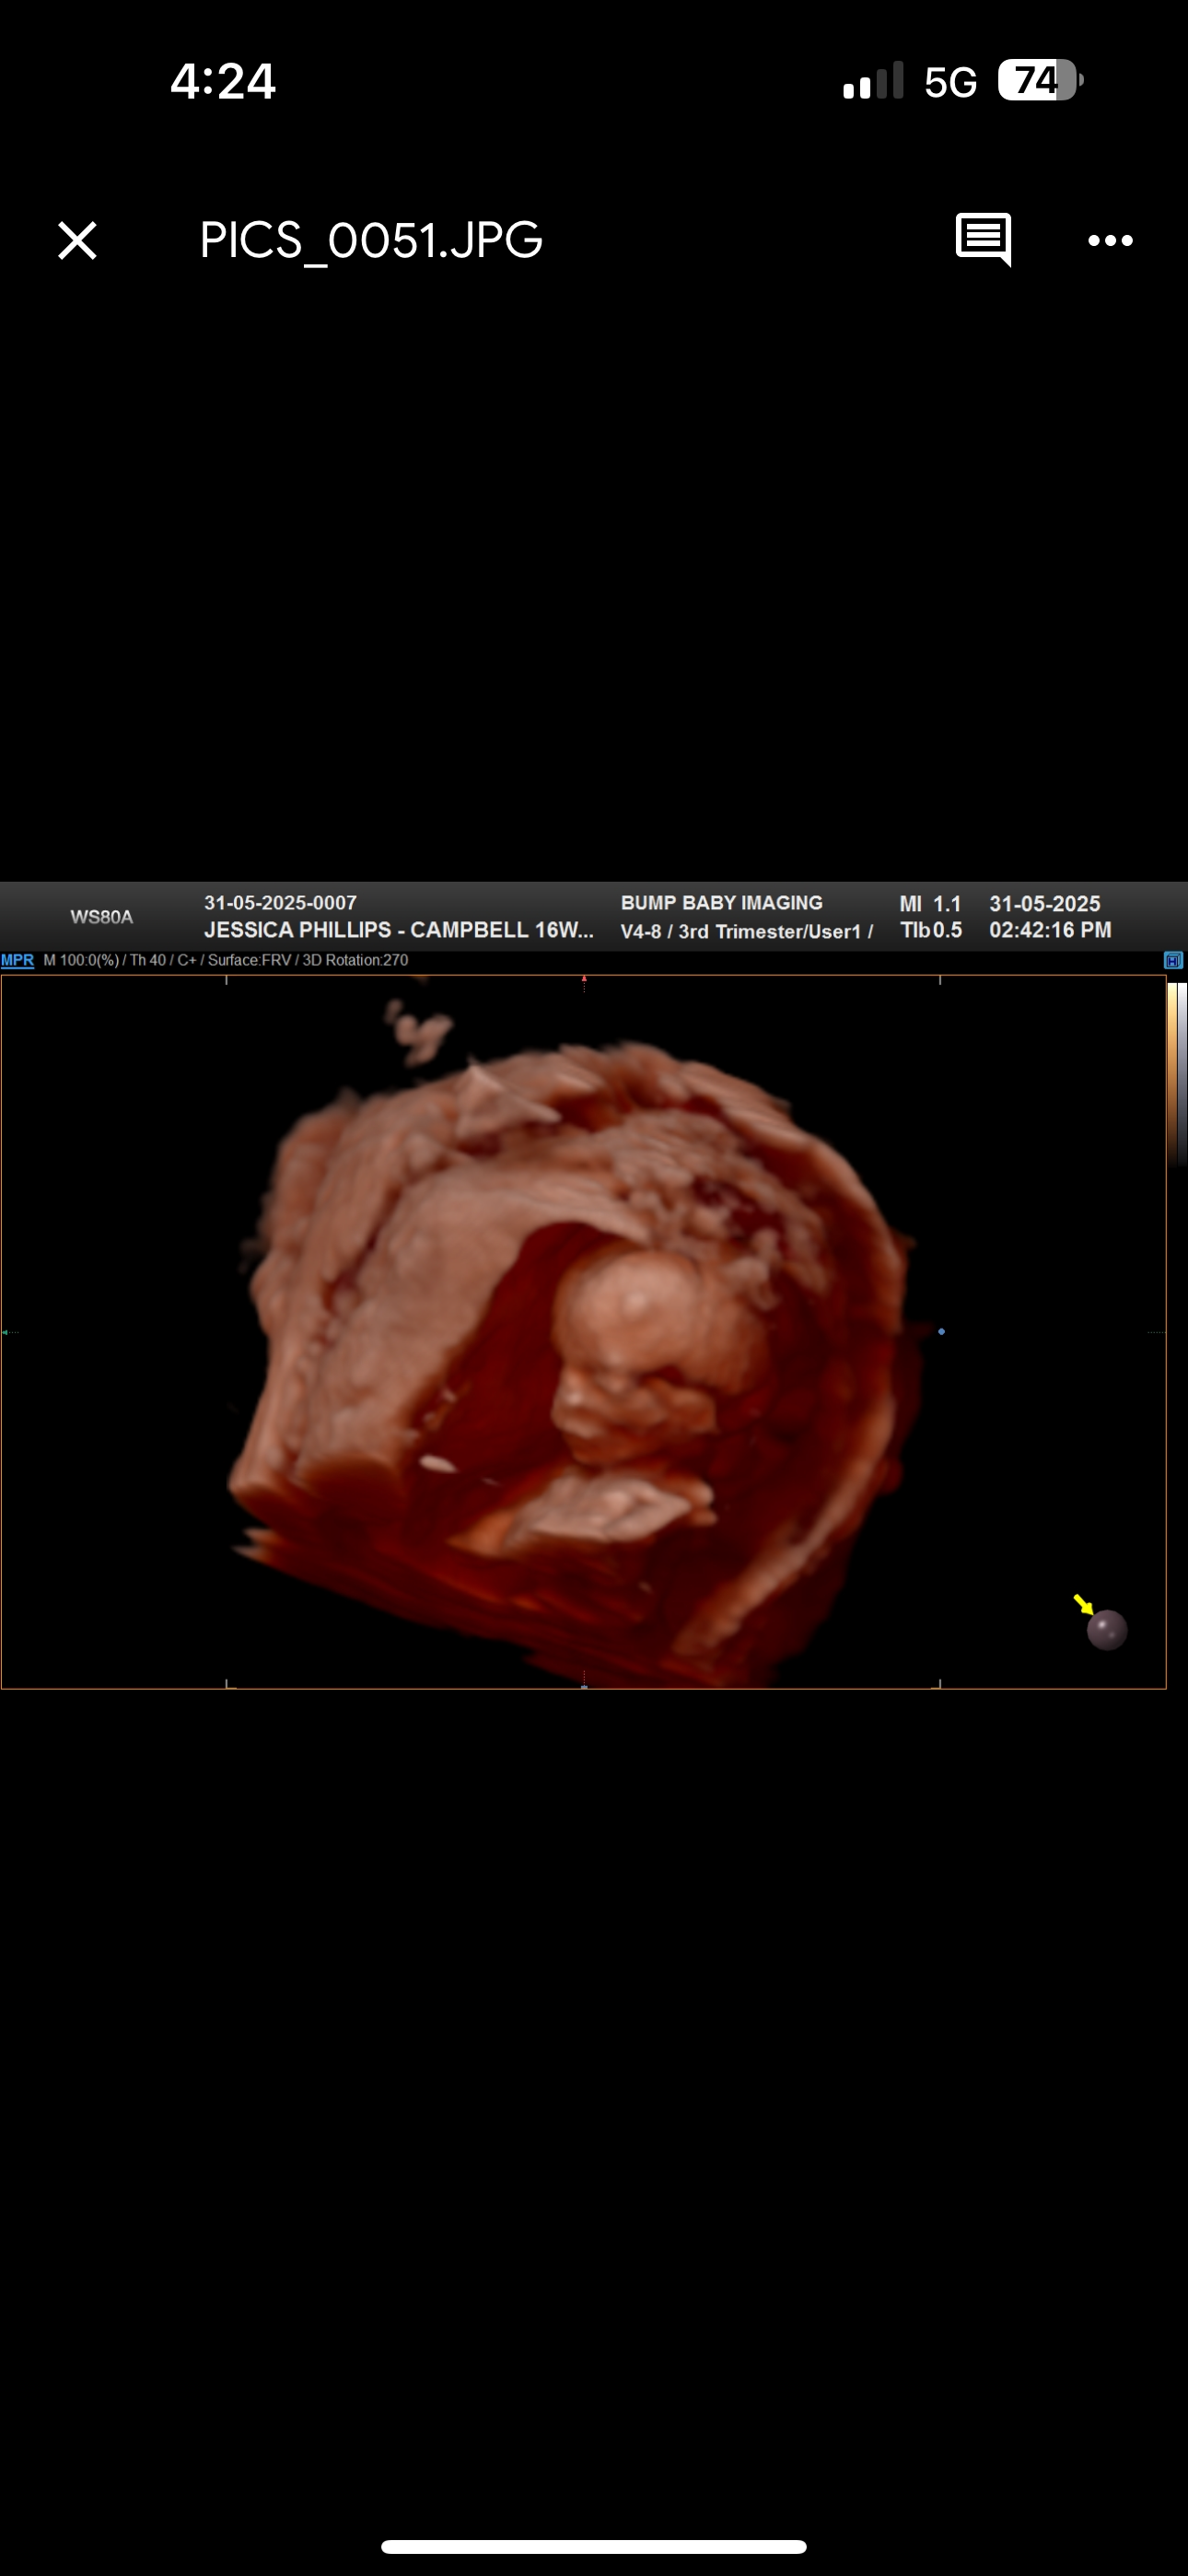

Hi, my name is Jess. I have my partner Jarrod & my beautiful son Jaxon. In March 2025, we found out we were expecting our beautiful girl Jayda Lavina Hickey in November 2025.

It wasn’t your typical pregnancy. I was in hospital twice in the first trimester due to 2 heavy bleeds. I was diagnosed with a hematoma. I was told both times I could miscarry.

I made it to the 12 week scan, where everything was perfect. She was how you’d expect any baby to be.

At my 20 week scan, that’s when it took a turn for the worst. We went in thinking we would walkout with a perfectly healthy baby & be able to go home and plan the rest of the what we needed to get and do for the rest of the pregnancy.

She had a lot of fluid on her brain. I went for a follow up scan 2 weeks later. We were told it was a possible stroke and brain bleed. They offered us termination. We didn’t go through with it, we went with more tests to get down to what exactly happened, what the outcome would be & possibly find out what caused it.

My baby girl has agenesis of the corpus callosum, a piece of her brain didn’t develop and she has a blockage in her brain which can’t drain the fluid and blood.